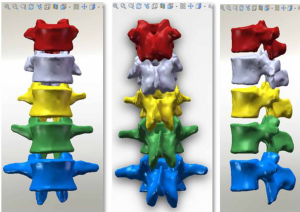

The three-dimensional entity model of T11–L3 and the screw-rod system were constructed using SolidWorks (Figures 7-9).

Models containing the implanted screw-rod system with five different defect sizes as well as five models with the screw-rod system removed were derived (defect diameters of 1/5, 2/5, 3/5, 4/5, and 5/5 of the anterior-two-thirds edge of the vertebral body, respectively) (Figure 12).